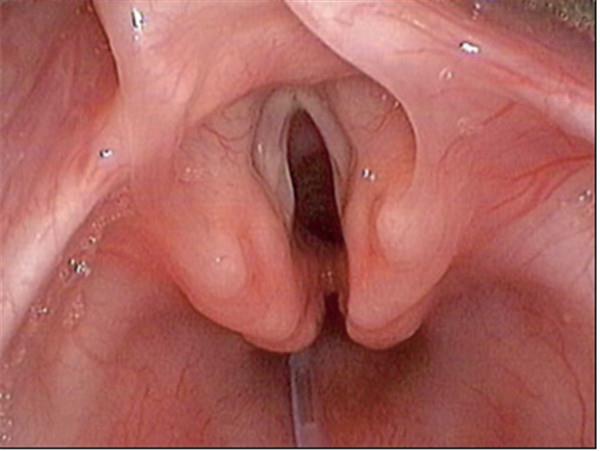

常見的鏡下改變:

喉裂